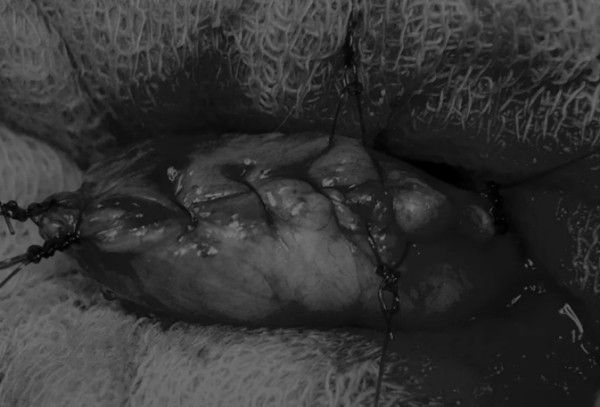

在牵引缝线之间选择血管扩张较差的区域用手术刀切开膀胱壁(图3)。在牵引缝合线之间用手术刀在血管不良的区域做切口。切开膀胱壁后,膀胱内的手术可按手术方案实施,例如取出结石(图4)。

图3 避开主要的膀胱血管,做一个尽可能小的切口

切口可以在膀胱背侧或腹侧进行,避免对大血管的损伤。